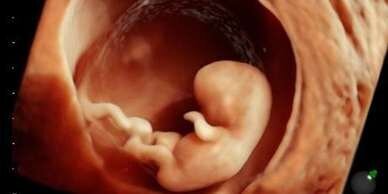

We can begin 2D imaging at 13 weeks. Ultrasound is most accurate for determining gender at 16 weeks and beyond. Because of this, gender determination will not be available before 16 weeks.

Perfect for when you just can't wait to see your baby or if you're dying to find out if it's a boy or girl! Baby is still quite small at this age, so face pictures are not yet clear.